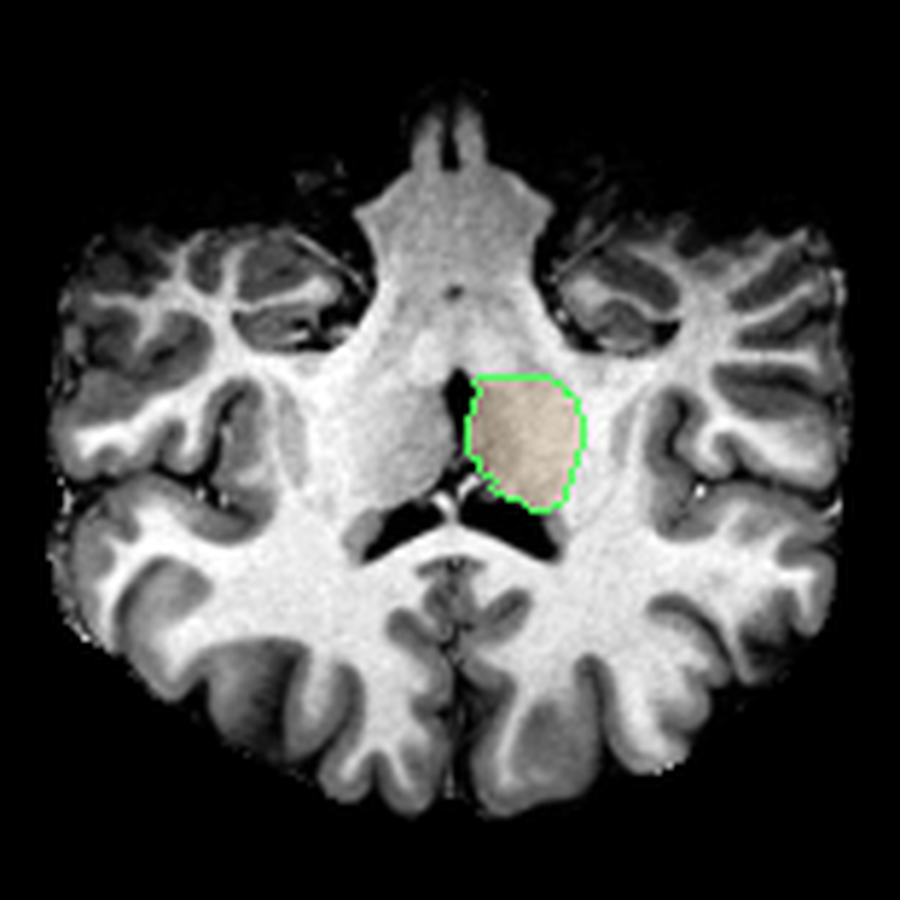

After the four-hour analysis, FreeSurfer had already given me what I needed to inspect the scan: a segmented volume that could be overlaid directly on the anatomical MRI. Visualising that (using a tool like ITK-SNAP), I got something a bit more interpretable than the original slices:

These are three orthogonal slices of my brain, with borders drawn around FreeSurfer’s own segmentations.

What I liked about having this data was that it changed how I interacted with the scan. Instead of staring at individual slices and guessing at the composition, I could start isolating specific parts of the brain.

The visualisations above show how little differentiation some brain regions have from their surroundings - I knew roughly where the thalamus was in the brain, but would never have been able to point it out on the MRI. At this stage, FreeSurfer plus some code had given me a perspective that would have been impossible for me to achieve myself.